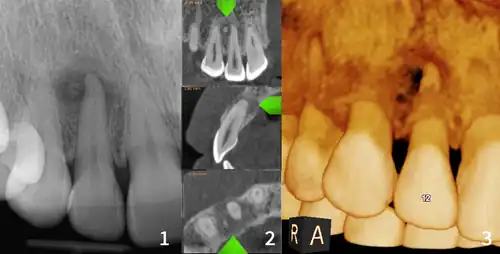

| Florid osseous dysplasia of the mandible | |

| Diagnostic method | X-ray, CBCT scan, vitality testing of teeth |

Diagnosis is important so that the treating doctor does not confuse it for another periapical disease such as rarefying osteitis or condensing osteitis. Incorrect diagnosis could lead to unnecessary root canal treatments. It can be diagnosed by radiographic appearance. Confirming the tooth is vital, as is noting the demographic (African American females).[1][2][3]